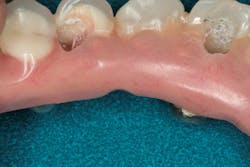

I removed the bridge to find the intaglio packed with food debris. The patient’s tissue was inflamed (figure 3), and she had developed a fungal infection. This could have been avoided with better presurgical preparation, adequate bone reduction, and proper vertical space development, which would have allowed the lab to make a hygienic intaglio (figure 4). Note the smooth and flowing intaglio surface in Figure 4. This is a bridge that can be easily maintained by the patient and hygienist.

Figure 4: Ideally convex intaglio surface for easy cleaning